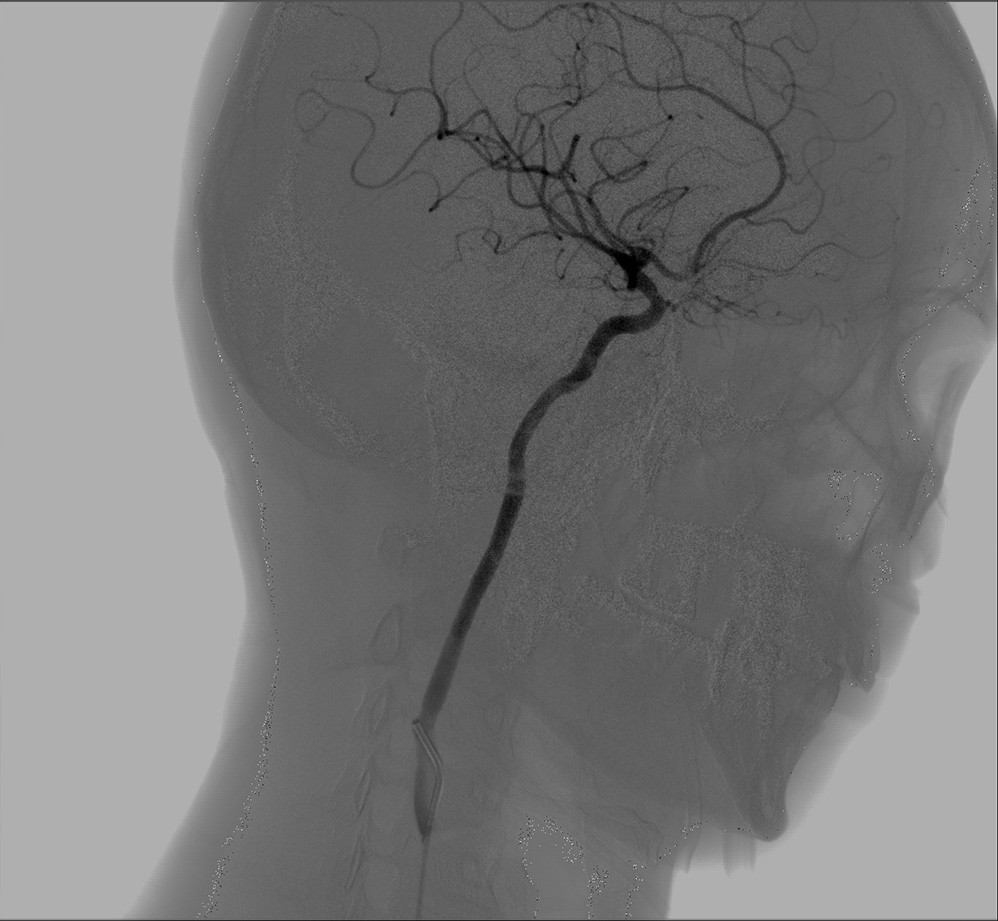

KD-C7100介入系列C形臂是由康达有着多年大型DSA研发经验的技术团队,在全新的非晶硅动态平板探测器技术基础上,自主研发的、可用于对外周血管进行造影检查及肿瘤介入治疗的一款移动式血管造影系统,是真正拥有药监局官方认定的具有介入资质的中C产品。

它所拥有的动态平板数字成像技术,以及床机一体化设计,使之成为一款更加贴合介入临床需求的移动式血管造影系统。它能够提供清晰的图像、丰富的分析工具及投照角度,先进的介入治疗工具与C臂系统协调一致,更加优化了血管外科、肿瘤科、ERCP、疼痛科等临床学科的介入手术使用环境,更具备微创医疗工作者所需要的便捷工作流和卓越影像,给用户以全新的视觉冲击和舒适的临床操控体验,是广大基层医院介入肿瘤科以及三甲医院专科介入(肝胆外科、妇科、ERCP室)使用的理想设备。

KD-C7100介入系列C形臂采用第二代大平板,它所特有的26×30CM的探测面积,能够对胸、腹、盆腔实现一次全覆盖,减少造影次数、降低辐射剂量,避免重叠遗漏、缩短手术时间。相当于12寸影增的有效成像区域,可以同时适用于外周血管介入及肿瘤介入,满足多科室的介入手术需求;兼具优秀DQE、高灵敏度及超高动态范围(16bit),使得获得图像更快、更清晰且无烧亮,同时剂量使用更低;2K的高清影像链,让每一个影像细节得以完美呈现。

KD-C7100介入系列C形臂,采用通过电离室实时测量X射线实际剂量的方式,快速调节KV、MA值实现X线设备的自动曝光控制,使临床医生能够在较短的时间内及时获取最优成像曝光参数,确保介入手术时数字电影大剂量曝光时的影像要求,为术者带来更多的便利。此外,采用全新的智能脉冲控制技术,智能调节脉冲宽度,它能够在不增加医患总吸收剂量的前提下,提高瞬时射线剂量从而提升图像质量。在相同射线条件下,脉冲方式连续工作3分钟相当于连续透视1分钟产生的热容量。